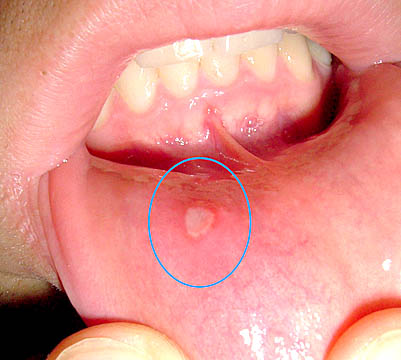

Áp tơ đơn giản

- Thường gặp (>85%).

- Thường một vết loét (<3).

- Vị trí: môi, má, lưỡi.

- Triệu chứng: Vết loét gây đau nhiều, <1cm, có viền viêm đỏ xung quanh.

- Lành thương 7-10 ngày, không để lại sẹo.